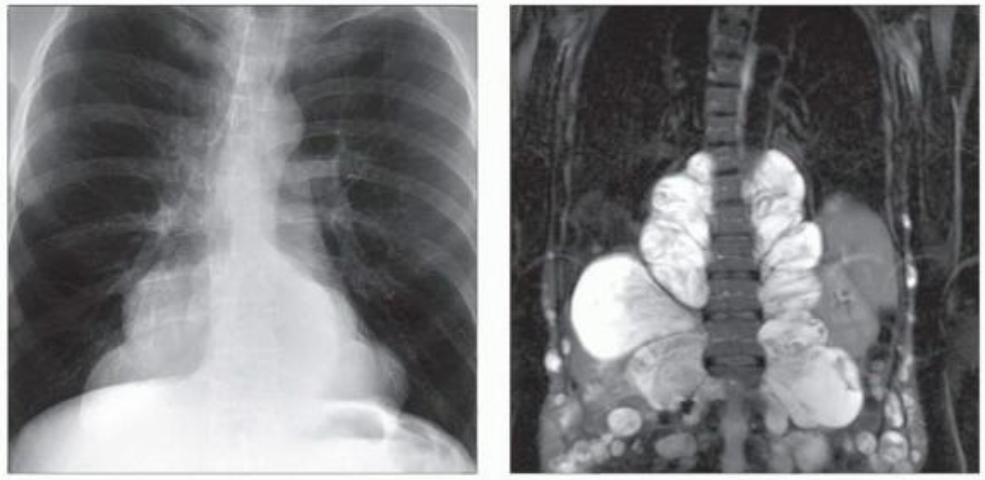

(左)PNST的形态学特征,表现为球形椎旁软组织肿块,可能产生良性压迫性骨质吸收和神经孔增宽。

(右)33岁女性,怀疑肺栓塞,冠状位CTA显示偶然发现右侧椎旁软组织肿块,不均匀强化,该肿块长入椎管并T8椎间孔扩大。活检证实了神经鞘瘤的诊断。